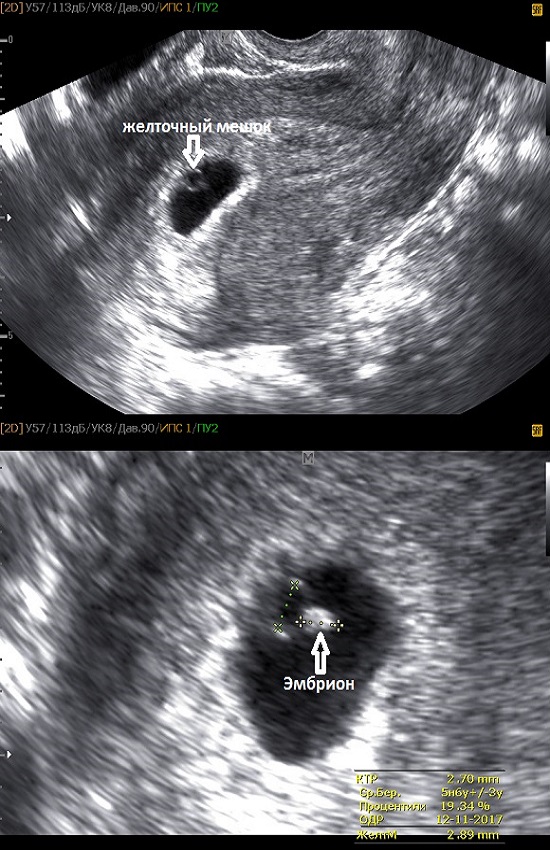

Развитие эмбриона: Что происходит на 3 неделе беременности